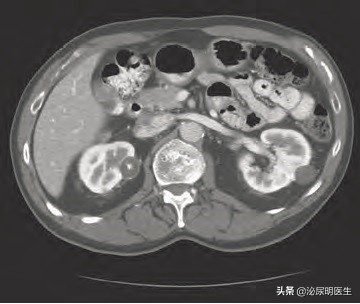

多囊肿的影像学表现B超为密集分布的液性暗区,如囊性结构过小也表现为无数异常的小回声复合体布满肾脏。CT表现双肾增大,肾呈分叶状,密布囊性结构,呈薄壁囊性结构。成人型多囊肾还可以做基因诊断,病变为16号染色体断臂,通过基因探针的方法做基因学确诊。

综上所述,单纯性肾囊肿和多囊肾的关系您看明白了吗?简单地说,如果B超CT上看到了肾囊肿之间有正常的肾实质一般认为是多发囊肿,而且个数即使是多发的,也会存在正常的肾实质,而多囊肾发病后则很难看到正常肾组织,且存在大大小小的囊肿,也就是说有大的、巨大的,中等的,小的,极小的,我们所说的囊肿爷爷、儿子、孙子、曾孙子都存在的病灶,而囊肿一般说来边界清楚,即时大小不一,也不像多囊肾那样密集恐惧症般的存在,在手术治疗和方法上更是明显不同,您看明白了吗?